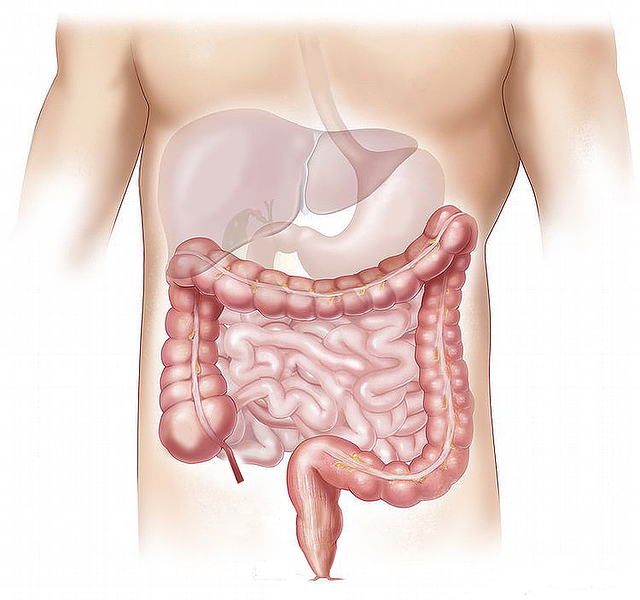

Informujemy, iż w najbliższy czwartek (12 grudnia) na Wydziale Żywienia Człowieka SGGW, ul. Nowoursynowska 159 C o godz. 17.15 w auli II, odbędzie się prelekcja dr. n med. Tadeusza Tarcikowskiego i dr Danuty Gajewskiej w ramach Wszechnicy Żywieniowej SGGW, której tematem będą choroby wątroby, ich diagnostyka i leczenie. Wstęp wolny.

Informujemy, iż 15 maja (środa) o godz. 17.15 na Wydziale Nauk o Żywieniu Człowieka i Konsumpcji SGGW, ul. Nowoursynowska 159 C (budynek nr 32, Aula II) odbędzie się w ramach Wszechnicy Żywieniowej w SGGW prelekcja pt: "Błonnik pokarmowy a zdrowie człowieka." z udziałem prof. dr hab. Joanny Gromadzkiej - Ostrowskiej i dr Joanny Rachtan - Janickiej. Wstęp wolny.

Informujemy, iż 10 kwietnia (środa) o godz. 17.15 na Wydziale Nauk o Żywieniu Człowieka i Konsumpcji SGGW, ul. Nowoursynowska 159 C (budynek nr 32, Aula II) odbędzie się w ramach Wszechnicy Żywieniowej w SGGW prelekcja pt: "Błonnik pokarmowy a zdrowie człowieka.", z udziałem dr hab. Jarosławy Rutkowskiej i dr Joanny Myszkowskiej-Ryciak. Wstęp wolny.

Informujemy, iż 20 lutego (środa) o godz. 17.15 na Wydziale Nauk o Żywieniu Człowieka i Konsumpcji SGGW, ul. Nowoursynowska 159 C (budynek nr 32, Aula II) odbędzie się w ramach Wszechnicy Żywieniowej w SGGW prelekcja pt. "Mikroflora przewodu pokarmowego a zdrowie człowieka", z udziałem dr Ewy Furstenberg, dr Małgorzaty Jałosińskiej i dr Doroty Zielińskiej. Wstęp wolny.